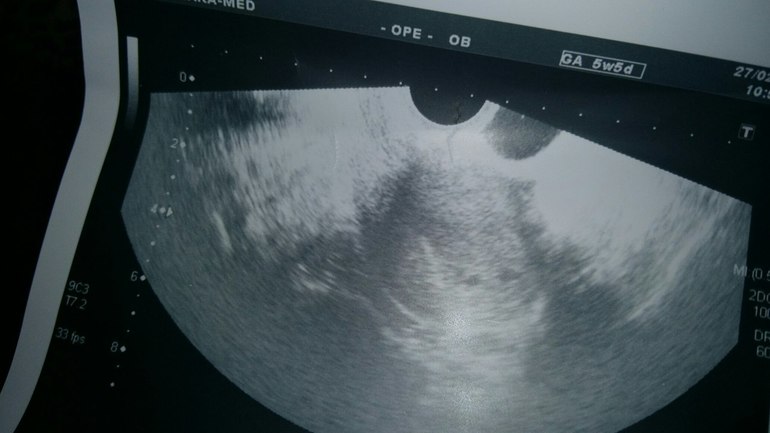

Девочки, что вы видите? это двойня или нет?

Были на узи. Поставили нам под вопросом двойню. Срок 3 недельки.Но врач сказала, что она не уверена. и добавила-тут либо двойня, либо угроза. Посмотрите, пожалуйста. Может у вас остались снимки с вашего узи, было бы интересно очень посмотреть. и любому мнению буду рада. Вот фото с узи

Тоже вижу три кружочка на втором снимке. У меня в 6-7 недель тоже были две точечки маленьких. А желточный мешок видно было на УЗИ, на снимке рано еще

Вижу даже три кружочка, два явно видно, и точечки внутри, третий мутный такой. В 7-8 нед будет понятно.

спасибо за ответ!)) третий на снимке видимо так получился. на экране вот было отчетливо 2 кружочка. но сказала, что это может быть и просто угроза... вот теперь бы дожить до следующего узи...))))

У меня в 3-4 недели было видно только одно плодное яйцо. В 7-8 уже было два. Но всякое бывает. Похоже, что у вас двойня...